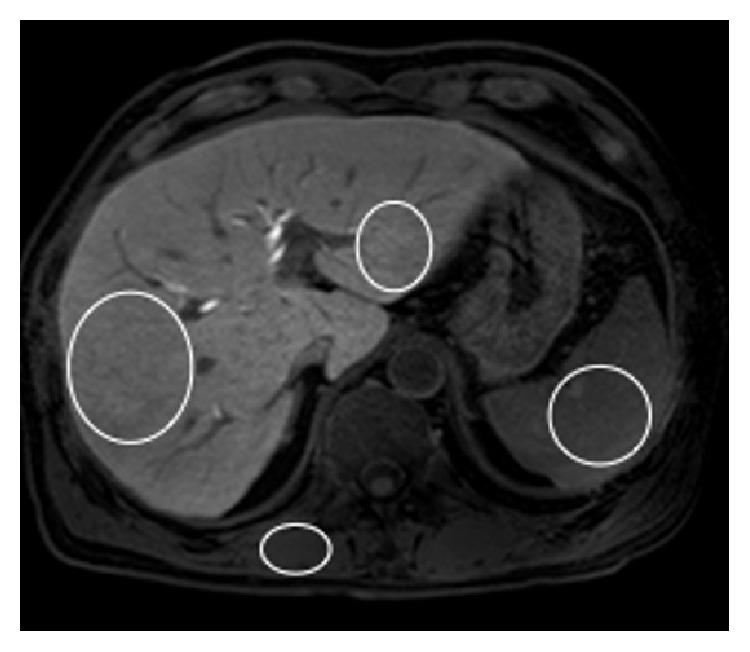

This retrospective study included 104 patients who underwent Gd-EOB-DTPA-enhanced MRI before liver surgery. For each patient, using the precontrast and hepatobiliary phase images, we calculated the increase rate of the liver-to-spleen signal intensity ratio (LSR), that is, the "ΔLSR," and the increase rate of the liver-to-muscle signal intensity ratio (LMR), that is, the "ΔLMR." ΔLSR × LV and ΔLMR × LV were also calculated. The correlation of each MR parameter with liver function data or liver pathology was assessed. The correlation coefficients were compared between ΔLSR (ΔLMR) and ΔLSR (ΔLMR) × LV.

方法

这项回顾性研究纳入了104例在肝脏手术前行Gd-EOB-DTPA增强MRI检查的患者。对于每位患者,利用平扫和肝胆期图像,我们计算了肝脾信号强度比(LSR)的增加率,即“ΔLSR”,以及肝肌信号强度比(LMR)的增加率,即“ΔLMR”。还计算了ΔLSR×LV和ΔLMR×LV。评估了每个磁共振参数与肝功能数据或肝脏病理的相关性。比较了ΔLSR(ΔLMR)与ΔLSR(ΔLMR)×LV之间的相关系数。